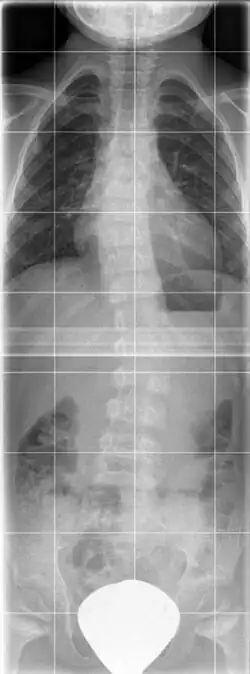

Im Röntgenbild findet sich eine generalisierte Platyspondylie, die verkürzten Röhrenknochen weisen eine Deformierung der Metaphyse hauptsächlich am Schenkelhals und der Trochanteren auf, häufig besteht eine Coxa vara.[2]